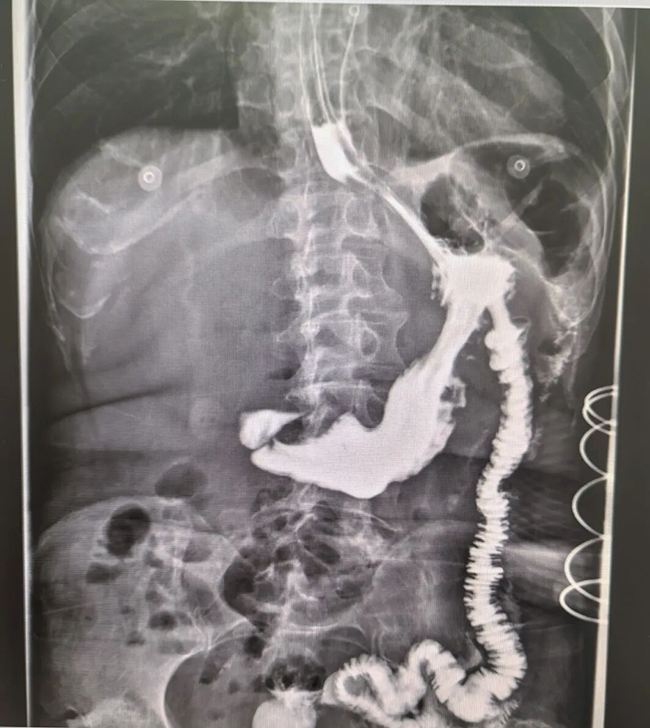

术后12小时上消化道造影